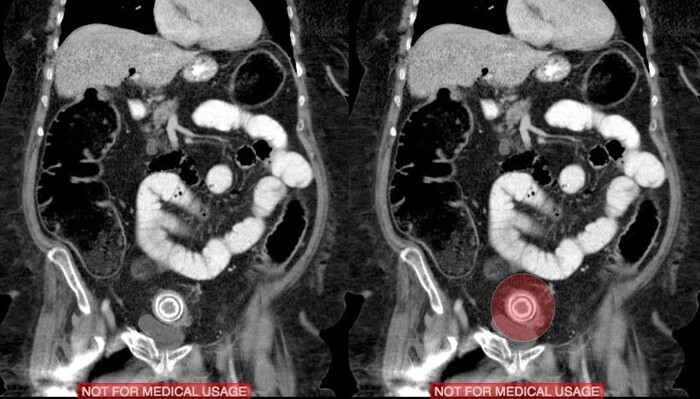

На 3й день после травмы из комы так и не вышла, посему сделали МРТ, на котором обнаружились участки повышенного сигнала на Т2-взвешенных изображениях на границе серого и белого вещества фронтально и темпорально справа, а также в область правого таламуса и в заднем отделе мозолистого тела т.н. сплениуме:

которые визуализировались и на FLAIR:

Очаги показывали также ограниченную диффузию на DWI-изображениях:

Ну и в довесок на SWI-изображениях (специальная импульсная последовательность, взвешенная по магнитной восприимчивости, усиливает сигнал от продуктов распада гемоглобина, что значительно повышает способность распознавать мельчайшие кровоизлияния в головном мозге) были выявлены очаги микрокровоизлияний в поражённых участках + в верхней ножке мозжечка и вдоль кортико-спинального тракта справа (чёрные пятна на изображениях):